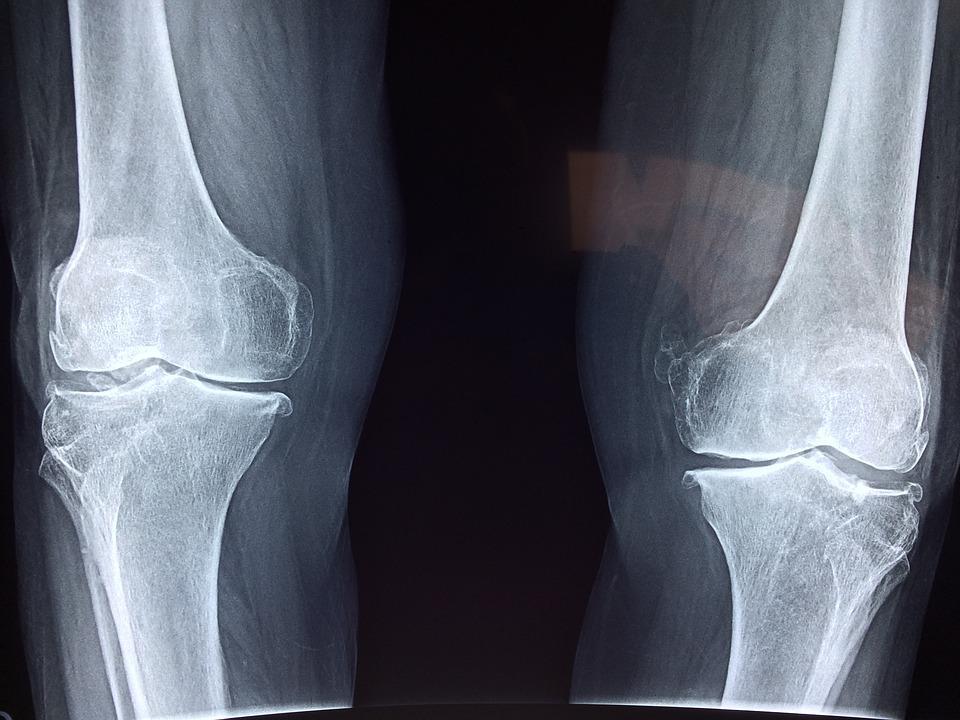

“회원님, 무릎이 안쪽으로 말려있어요 바깥쪽 근육이 없어서 그런 건데 그런 다리들이 잘 넘어지거든요, 그리고 나중에 관절염 오기가 쉬워서 엉덩이 근육을 키워야 그나마 보완이 돼요.”

싶었지만 하체운동을 할 때마다 내 의지와는 상관없이 자꾸 안쪽으로 말리는 무릎을 보니 정말 그런가 싶었다. 자주 쓰는 근육에 따라 몸이 맞춰서 적응했기 때문이라고 했다.